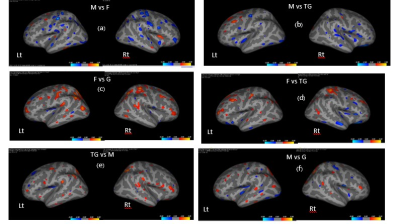

Fig. 2 Blue in (a) and (b) demonstrated significantly thinner areas in M compared with F and TG. F showed thicker cortical structures compared with G and TG, (c) and (d) (orange). Increase thickness in TG to M, (e). Mixed regions, (f).